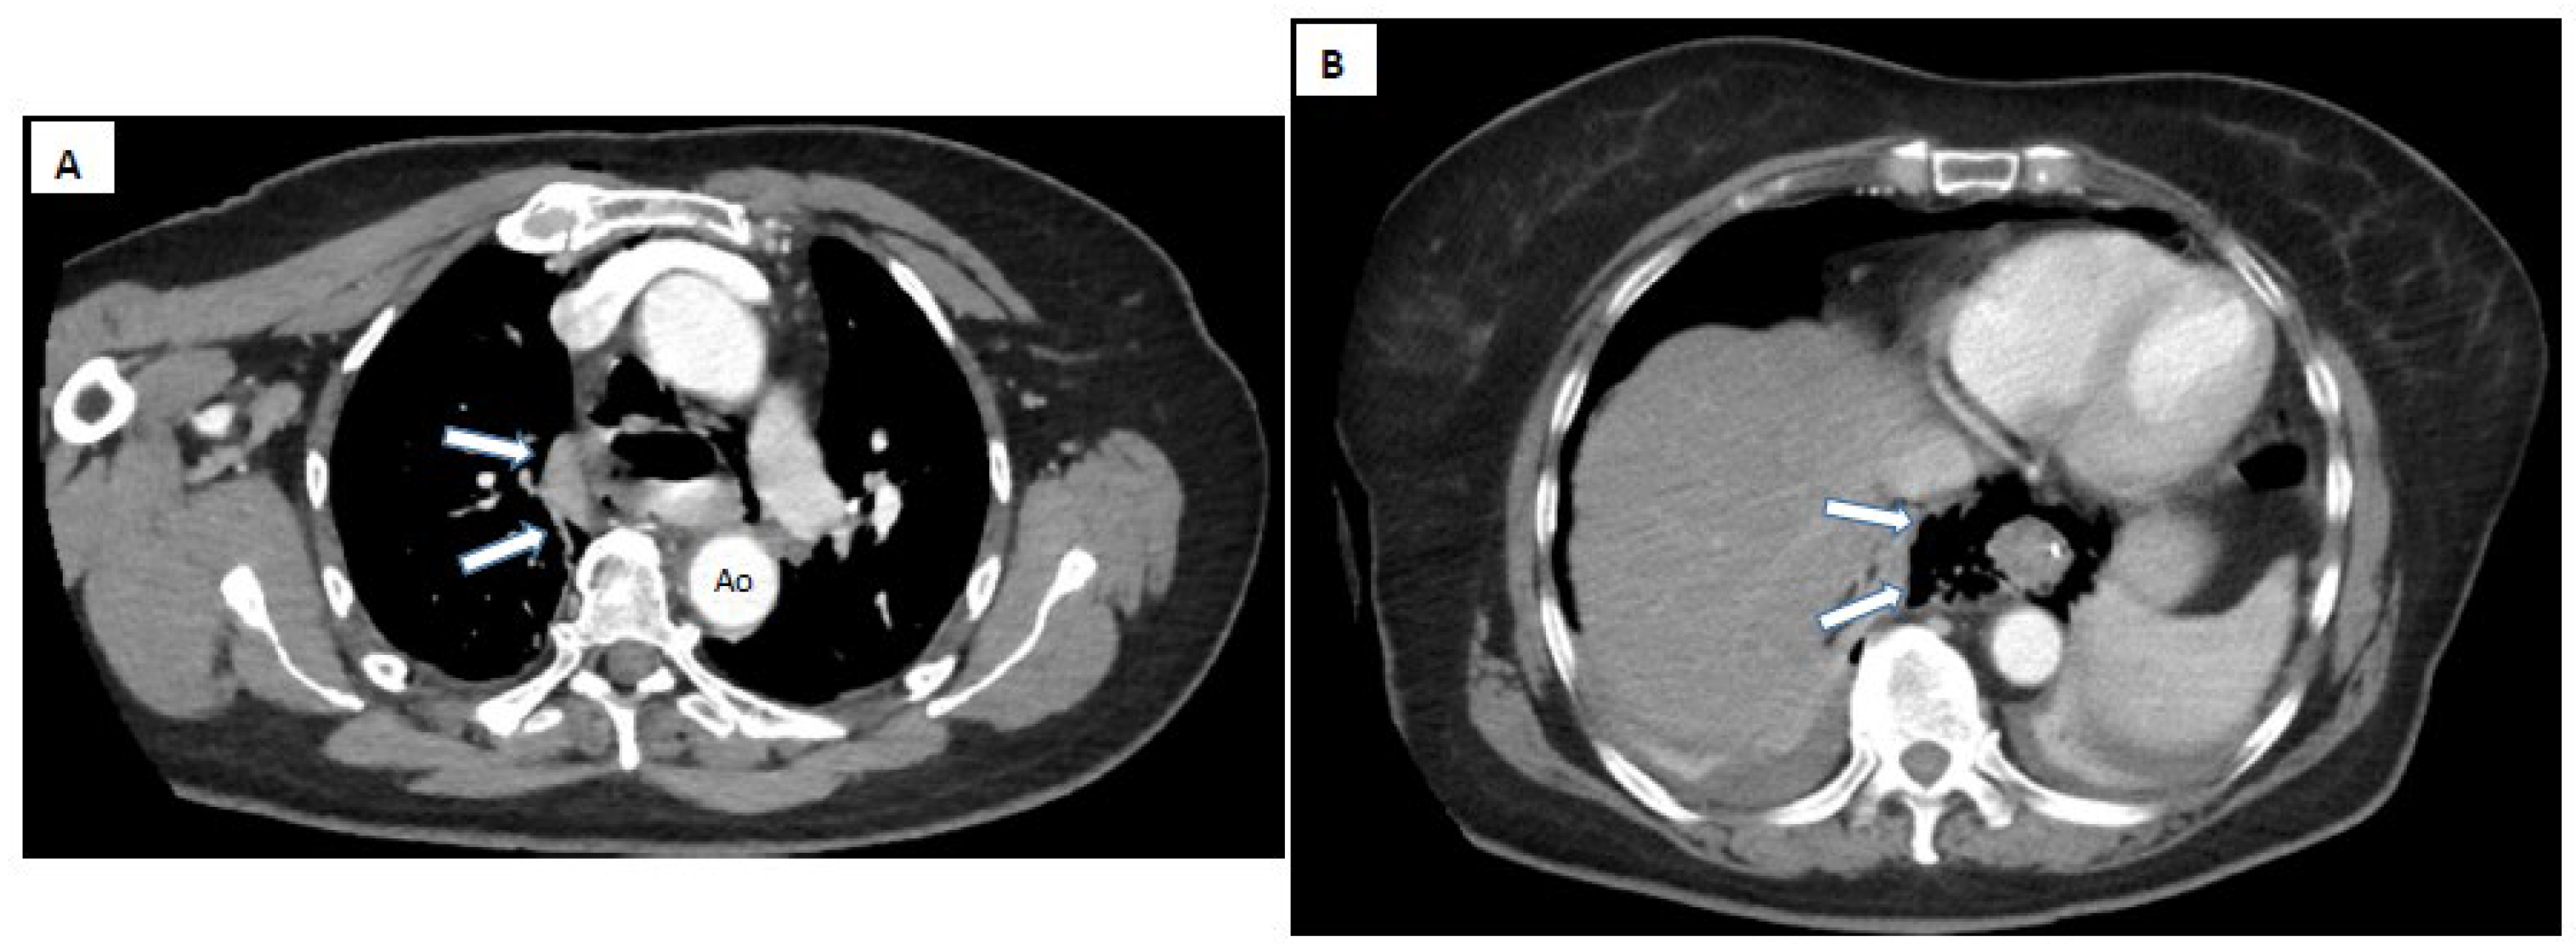

8. Paraclinical Investigations

- Pneumomediastinum

- Localized periaortic gas

- Mediastinal fluid collections

- Thickened esophageal wall

- Gas within thoracic soft tissues, neck, or around major vessels

- Oral contrast extravasation from the esophageal lumen [10].